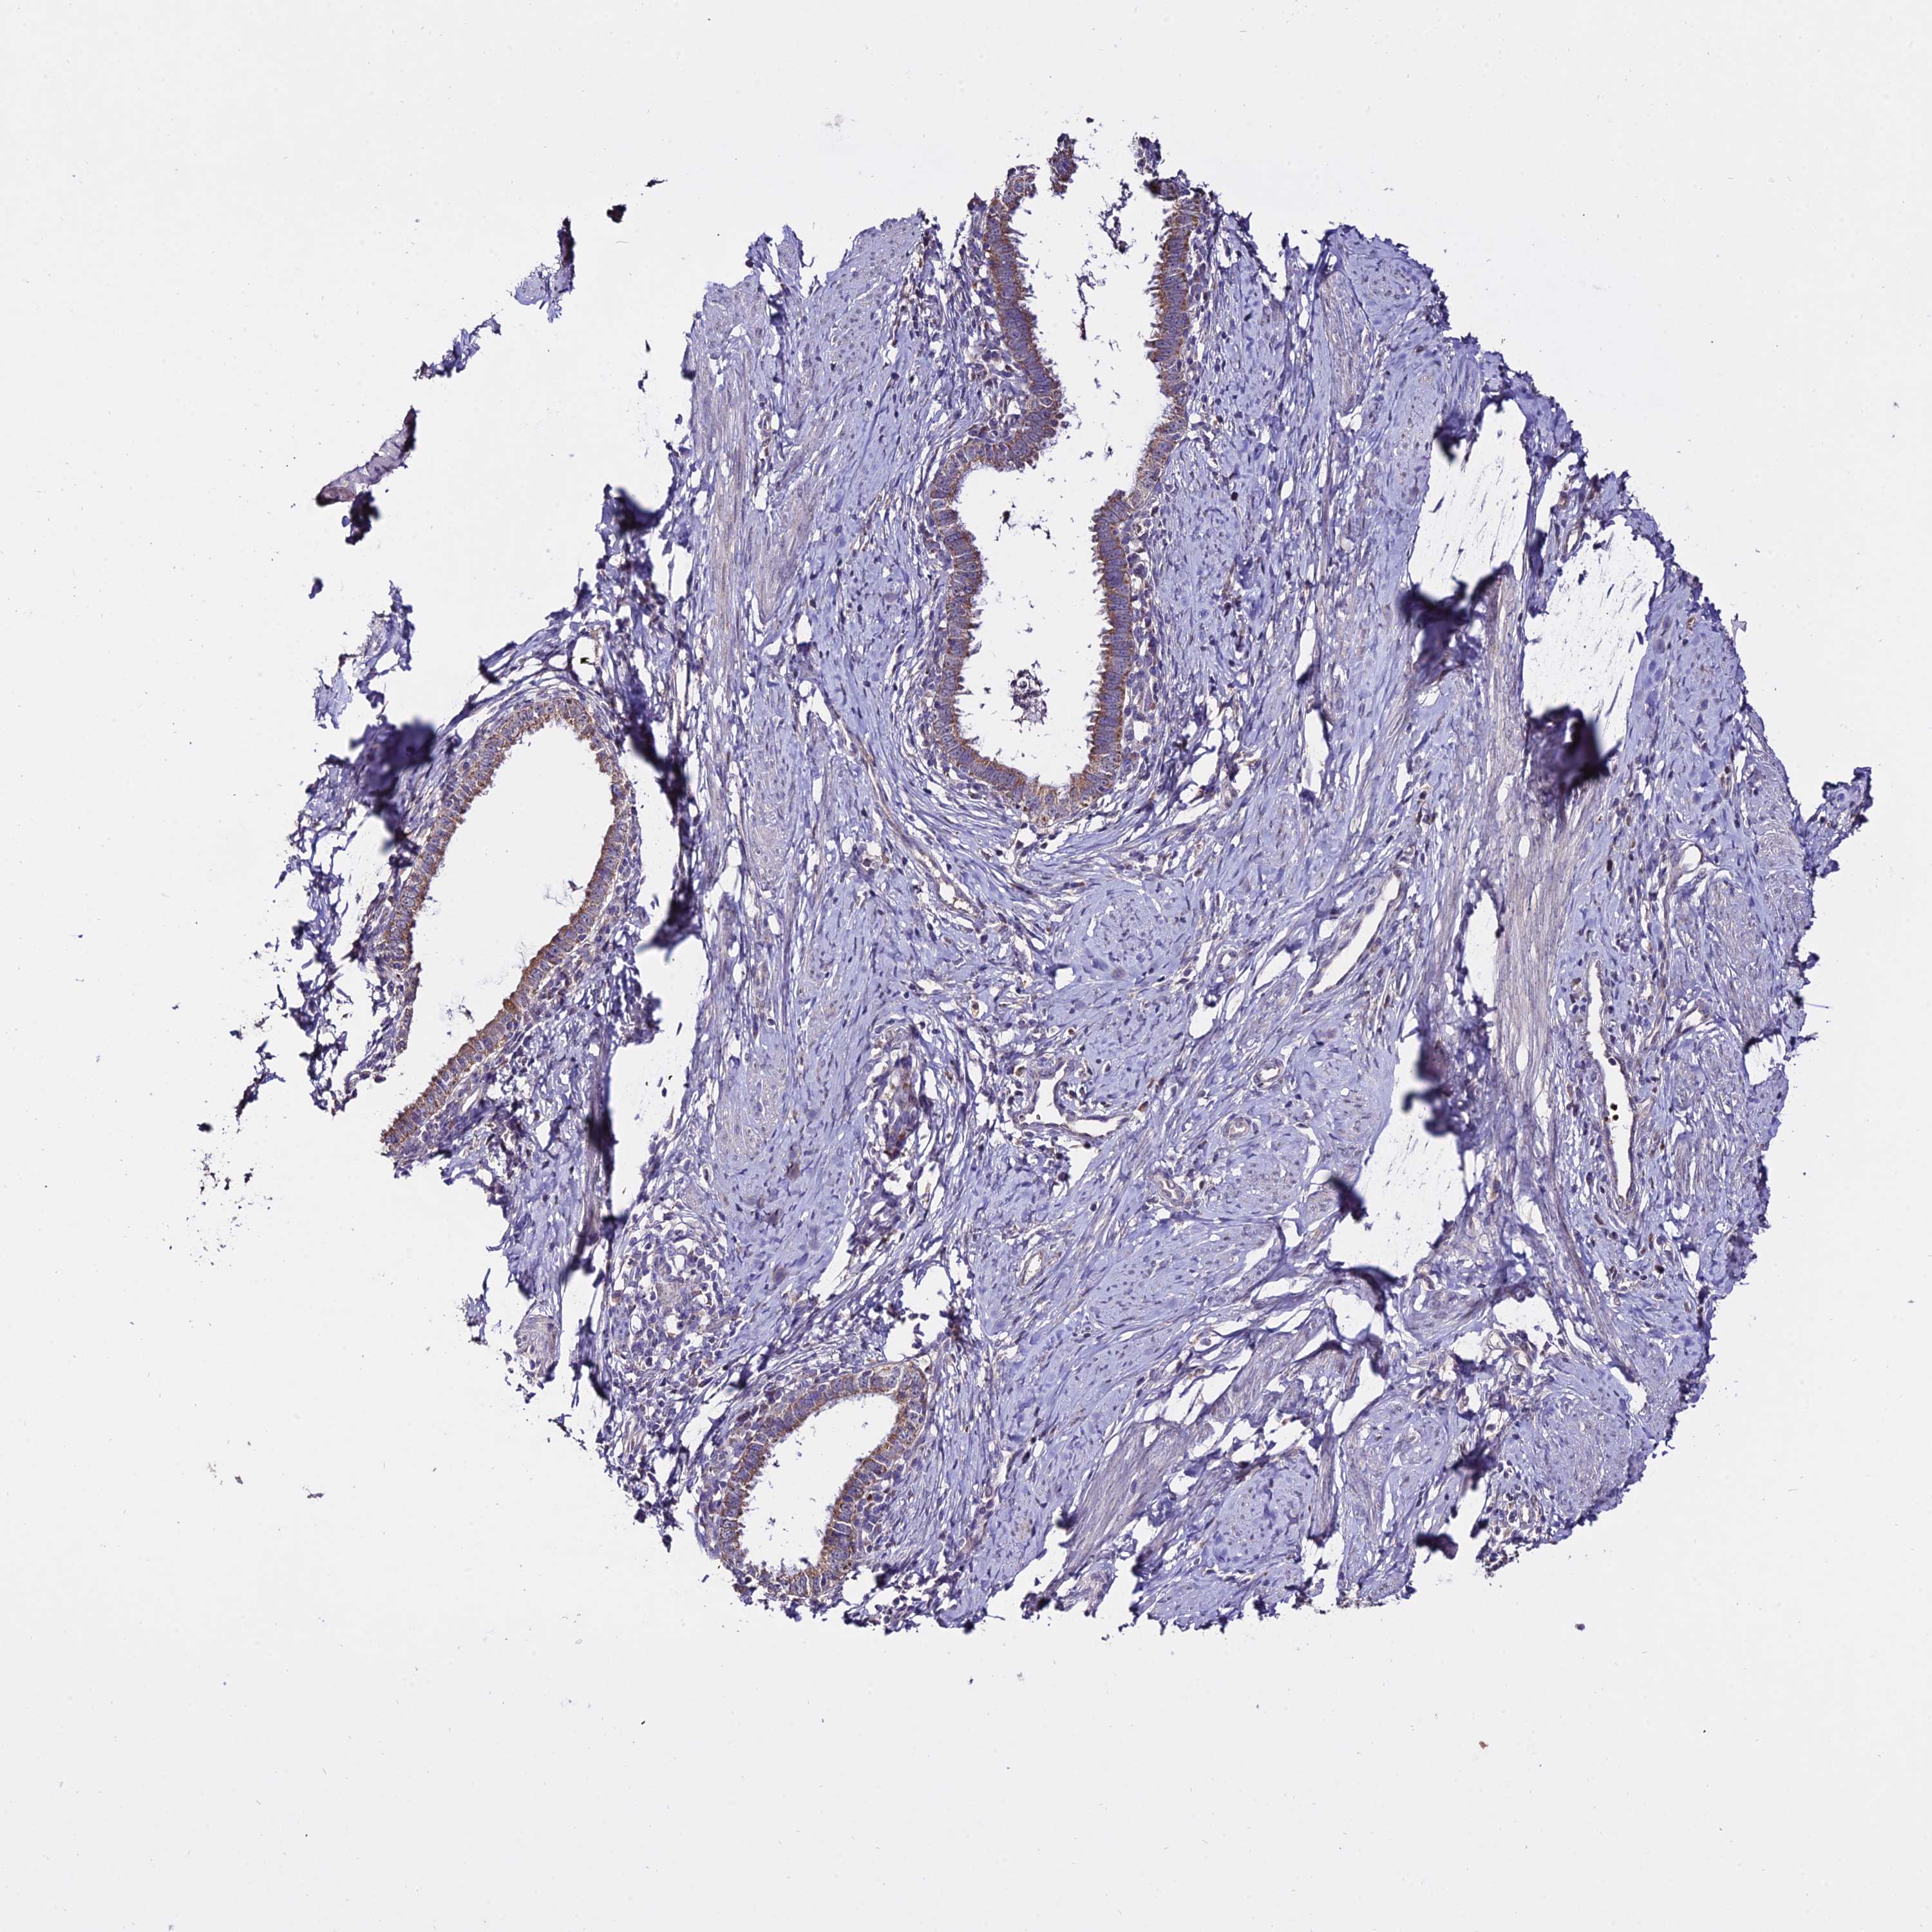

CERVICAL CANCER - Protein expressioni

A mouse-over function shows sample information and annotation data. Click on an image to view it in a full screen mode. Samples can be filtered based on level of antibody staining by selecting one or several of the following categories: high, medium, low and not detected. The assay and annotation is described here.

Note that samples used for immunohistochemistry by the Human Protein Atlas do not correspond to samples in the TCGA dataset.

Antibody stainingi

Antibody staining in the annotated cell types in the current human tissue is reported as not detected, low, medium, or high, based on conventional immunohistochemistry profiling in selected tissues. This score is based on the combination of the staining intensity and fraction of stained cells.

Each image is clickable and will lead to virtual microscopy that enables deeper exploration of all samples and also displays staining intensity scores, fraction scores and subcellular localization as well as patient and tissue information for each sample.

Antibody HPA042994

Staining

High

Medium

Low

Not detected

Intensity

Strong

Moderate

Weak

Negative

Quantity

>75%

75%-25%

<25%

None

Location

Nuclear

Cytoplasmic/membranous

Cytoplasmic/membranous,nuclear

Squamous cell carcinoma, NOS

Adenocarcinoma, NOS